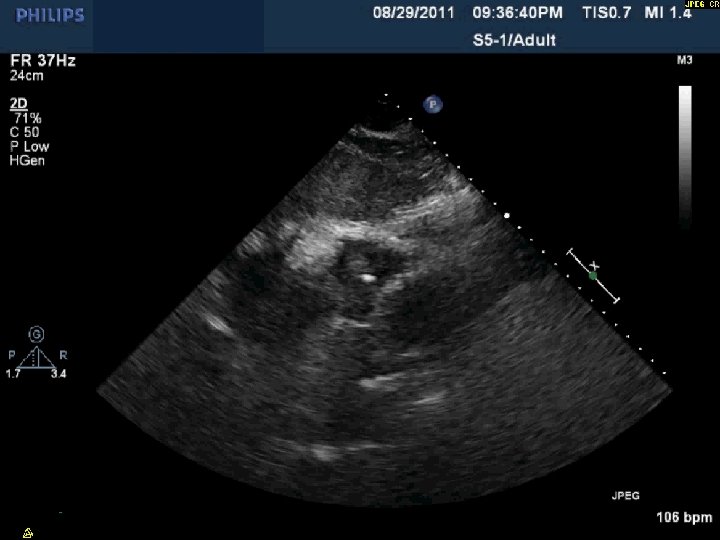

Day 2 No further pericardial drainage, echo without effusion…pericardial catheter pulled Day 3 Enoxaparin

Day 2 No further pericardial drainage, echo without effusion…pericardial catheter pulled Day 3 Enoxaparin for DVT prophylaxis initiated 8 hours later, PEA arrest Echo shows recurrence of effusion and tamponade physiology

Day 2 Stable overnight No further pericardial drainage Echo shows no recurrence of effusion

Day 2 Stable overnight No further pericardial drainage Echo shows no recurrence of effusion In ICU, pericardial pigtail catheter pulled…. . Within 5 minutes, systolic blood pressure drops to <80 and bedside echo confirms recurrence of effusion Emergency pericardiocentesis draws off 650 cc immediately followed by continuous drainage of blood